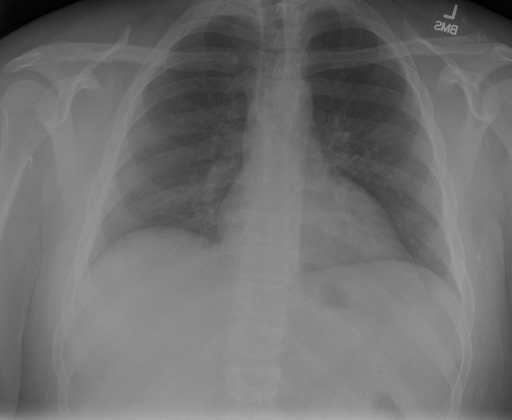

## 本文贡献  - 借助ChatGPT以及公开的数据集,我们构造了一个`X光影像-诊断报告`对的医学多模态数据集; - 我们将构建的中文胸部X光片诊断数据集在[VisualGLM-6B](https://github.com/THUDM/VisualGLM-6B)进行微调训练,并开放了部分训练权重用于学术研究; ## 数据集 - [MIMIC-CXR](https://physionet.org/content/mimic-cxr-jpg/2.0.0/)是一个公开可用的胸部X光片数据集,包括377,110张图像和227,827个相关报告。 - [OpenI](https://openi.nlm.nih.gov/faq#collection)是一个来自印第安纳大学医院的胸部X光片数据集,包括6,459张图像和3,955个报告。 在上述工作中,报告信息都为非结构化的,不利于科学研究。为了生成合理的医学报告,我们对两个数据集进行了预处理,并最终得到了可以用于训练的**英文报告**。除此之外,为了更好的支持中文社区发展,借助ChatGPT的能力,我们将英文报告进行了中文翻译,并最终形成了可用于训练的数据集。 |数据集|数量|下载链接| |:-|:-|:-| |MIMIC-CXR-zh|-|-| |OpenI-zh|6,423|[诊疗报告(英文)](./data/openi-en.json)、[诊疗报告(中文)](./data/Xray/openi-zh.json) 、[X光影像](https://pan.baidu.com/s/13GBsDMKf6xBZBSHpoWH_EA?pwd=k9sh)| ## 快速上手 ### 1.安装环境 ```bash # 安装依赖 pip install -r requirements.txt # 国内换源安装依赖 pip install -i https://mirrors.aliyun.com/pypi/simple/ -r requirements.txt ``` 此时默认会安装`deepspeed`库(支持`sat`库训练),此库对于模型推理并非必要,同时部分`Windows`环境安装此库时会遇到问题。 如果想绕过`deepspeed`安装,我们可以将命令改为: ```bash # 安装依赖 pip install -i https://mirrors.aliyun.com/pypi/simple/ -r requirements_wo_ds.txt # 安装SwissArmyTransformer pip install -i https://mirrors.aliyun.com/pypi/simple/ --no-deps "SwissArmyTransformer>=0.3.6" ``` ### 2.模型推理 |模型权重|下载链接| |:-|:-| |checkpoints-XrayGLM-300|-| |checkpoints-XrayGLM-3000|-| CLI推理: ```python python cli_demo.py --from_pretrained checkpoints/checkpoints-XrayGLM-3000 --prompt_zh '详细描述这张胸部X光片的诊断结果' ``` 更多[参数](https://github.com/WangRongsheng/XrayGLM/blob/main/cli_demo.py#L16) ### 3.模型训练(复现XrayGLM) > 我们所使用的硬件为:四卡A100 80GB - (1)准备[诊疗报告(中文)](./data/Xray/openi-zh.json)和[X光影像](https://pan.baidu.com/s/13GBsDMKf6xBZBSHpoWH_EA?pwd=k9sh)在`data/Xray`文件夹下; - (2)开始训练: ```bash # 设置CUDA变量,主要是为了解决有时候直接训练而出现无法正确加载到显卡问题 export CUDA_VISIBLE_DEVICES=0,1,2,3 # 开始训练 bash finetune_XrayGLM.sh ``` 这里的复现过程非常简单,主要是很多过程我们都为大家准备好了,大家可以随时复现一个自己的`XrayGLM`。 ### 4.模型训练(通用) ## 效果展示 影像诊断: |X光影像|诊疗报告(医生)|XrayGLM| |:-|:-|:-| ||根据X射线图像,心脏大小正常,肺部看起来很清晰。已经排除了肺炎、积液、水肿、气胸、腺病、结节或肿块的存在。该发现表明一切正常。换句话说,总体印象是胸部正常。|X光片显示,心脏大小正常。肺部没有气胸或胸腔积液的证据。骨骼结构看起来没有任何异常。总的来说,X光片表明没有发现急性心肺疾病的迹象。| ||X光图片显示没有扭曲的区域、可疑的骨质不透明度或胸腺积液。心脏大小轻微增大,但非常稳定。此外,没有气胸的证据,肺野也正常。总体来说,X光片显示没有急性心脏异常,但要注意轻微的心脏扩大。|X光片显示,心脏大小正常。肺部和纵隔轮廓清晰,没有气胸或胸腔积液的证据。骨骼结构完整,没有任何急性异常。| ||心影形态在正常范围内。没有急性骨质异常。有可能出现没有明显的吸水或肺实质状况的线索。没有大面积积液或气胸。有可能怀疑其有误吸或肺实质问题。为了确诊和治疗,可能需要进行适当的影像学随访。|心脏大小正常,肺部和纵隔轮廓清晰。没有急性异常或活动受限的证据。没有任何明显的气胸、胸腔积液或肺不张的迹象。此外,也没有发现任何局灶性骨质异常或其他急性疾病。| 多轮对话: |X光影像|诊疗报告(医生)| |:-|:-| ||右侧主动脉突出观察到。心脏大小正常。胸部未发现明显的肺气肿、胸膜积液或可疑的肺部病变。报告指出已知右侧主动脉情况正常。| ```bash >> X光影像路径:./data/Xray/861_1.png >> 用户:这是一张什么图? >> XrayGLM:这张图片显示的是一张肺部检查的X光片。 >> 用户:请描述这张胸部X光片的诊断结果 >> XrayGLM:心脏大小正常,肺部清晰。没有急性心肺疾病的证据。 >> 用户:是否存在肺气肿? >> XrayGLM:没有肺气肿。心脏大小正常,肺部清晰。没有发现急性心肺疾病的证据。 >> 用户:平时饮食该注意什么? >> XrayGLM:饮食应该健康,均衡。建议增加蛋白质的摄入量,因为蛋白质有助于维持肌肉和骨骼的健康。多食用蔬菜、水果、全谷物以及健康的脂肪来源如橄榄油、鱼类等可以帮助获得足够的维生素和矿物质。此外,避免过度饮酒或吸烟,这些习惯可能会对心脏健康产生负面影响。 ``` ## 未来展望 1. 模型的能力更多来源于数据的支持,`OpenI-zh`作为微调数据集,其数据量足以支持研究,在更广泛的任务和性能表现上,我们认为**在大规模数据集上预训练并在高质量少量数据集上微调是一种可行的方案**; 2. 普遍意义的理解上,视觉多模态模型=视觉模型+语言模型。除了需要关注视觉模型信息与语言模型输出的搭配外,还需要**额外关注到语言模型的加强,在人机的对话中,尤其是医疗语言模型的问答上,除了专业的医疗问题回答,带有人文情怀的有温度的回答更应该是我们追寻的目标**。 ## 项目致谢 1. [VisualGLM-6B](https://github.com/THUDM/VisualGLM-6B)为我们提供了基础的代码参考和实现; 2. [MiniGPT-4](https://github.com/Vision-CAIR/MiniGPT-4)为我们这个项目提供了研发思路; 3. ChatGPT生成了高质量的中文版X光检查报告以支持XrayGLM训练; 4. [gpt_academic](https://github.com/binary-husky/gpt_academic)为文档翻译提供了多线程加速; 5. [MedCLIP](https://github.com/RyanWangZf/MedCLIP) 、[BLIP2](https://huggingface.co/docs/transformers/main/model_doc/blip-2) 、[XrayGPT](https://github.com/mbzuai-oryx/XrayGPT) 等工作也有重大的参考意义;  这项工作由[澳门理工大学应用科学学院](https://www.mpu.edu.mo/esca/zh/index.php)硕士生[王荣胜](https://github.com/WangRongsheng) 、[段耀菲](https://github.com/IsBaSO4) 、[李俊蓉](https://github.com/lijunrong0815)完成,指导老师为檀韬副教授、[彭祥佑](http://www.patrickpang.net/)老师。 *特别鸣谢:[USTC-PhD Yongle Luo](https://github.com/kaixindelele) 提供了有3000美金的OpenAI账号,帮助我们完成大量的X光报告翻译工作 ## 免责声明 本项目相关资源仅供学术研究之用,严禁用于商业用途。使用涉及第三方代码的部分时,请严格遵循相应的开源协议。模型生成的内容受模型计算、随机性和量化精度损失等因素影响,本项目无法对其准确性作出保证。即使本项目模型输出符合医学事实,也不能被用作实际医学诊断的依据。对于模型输出的任何内容,本项目不承担任何法律责任,亦不对因使用相关资源和输出结果而可能产生的任何损失承担责任。 ## 项目引用 如果你使用了本项目的模型,数据或者代码,请声明引用: ```bash @misc{wang2023XrayGLM, title={XrayGLM: The first Chinese Medical Multimodal Model that Chest Radiographs Summarization}, author={Rongsheng Wang, Yaofei Duan, Junrong Li, Patrick Pang and Tao Tan}, year={2023}, publisher = {GitHub}, journal = {GitHub repository}, howpublished = {\url{https://github.com/WangRongsheng/XrayGLM}}, } ``` ## 使用许可 此存储库遵循[CC BY-NC-SA](https://creativecommons.org/licenses/by-nc-sa/4.0/) ,请参阅许可条款。